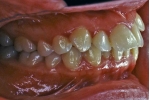

日本矯正歯科学会専門医課題症例(第3症例)

カテゴリー:Class Ⅱ division 1(抜歯症例)

| 初診時